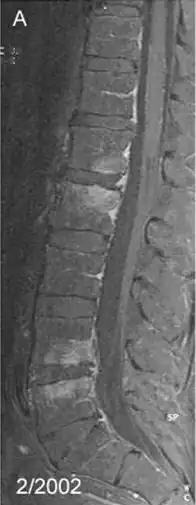

Spondylitis due to Tropheryma whipplei: Contrast-enhanced, T1 weighted fat suppressed magnetic resonance imaging demonstrating contrast enhancing lesions of spondylitis in the first (L1) and second (L2), as well as fourth (L4) and fifth (L5) lumbar vertebra, sparing the intervertebral discs